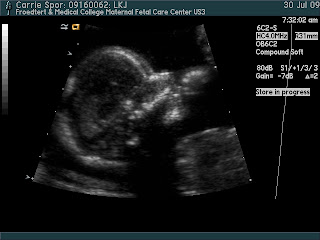

For those of you that haven't heard yet-yes, I (Carrie:) am pregnant. I had an ultrasound today and the ultrasound tech said she didn't see any boy parts, so it's a girl!

Everything looks good, except they moved my due date 2 weeks back:-/ According to the size today I am due Dec. 29. What a cute little Christmas present!